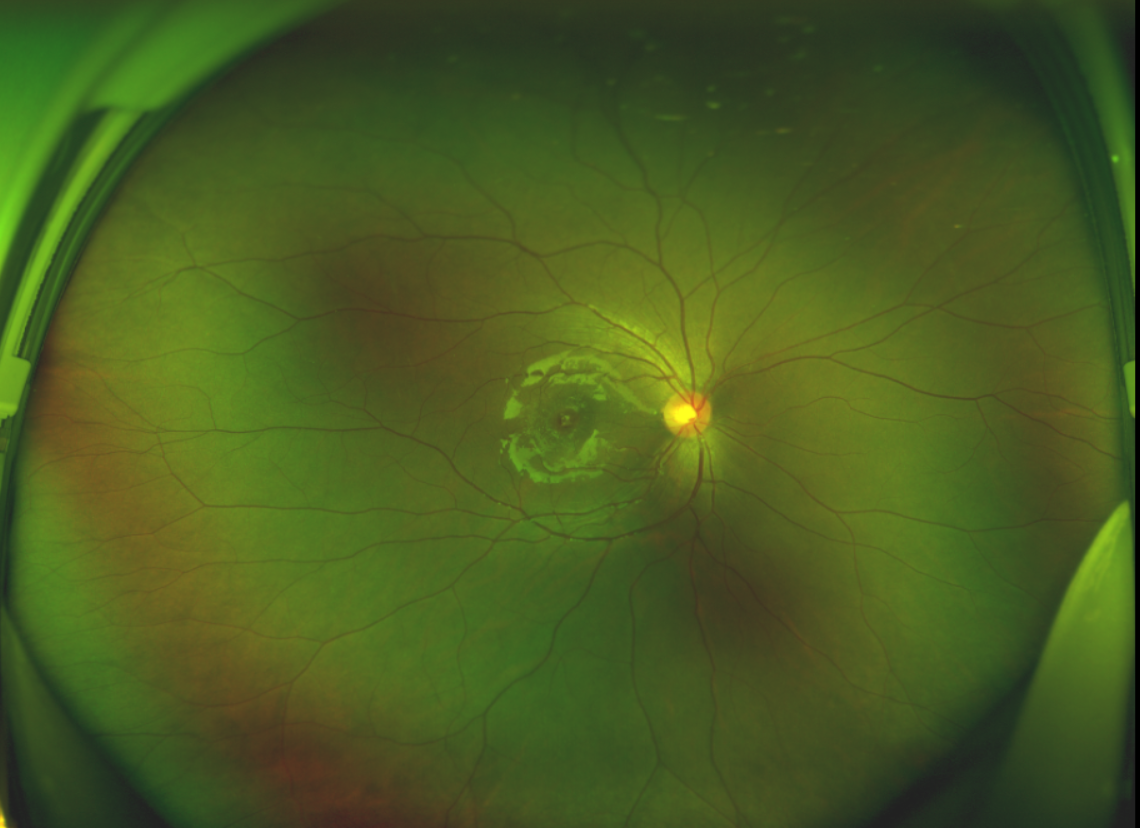

黃斑位于視網(wǎng)膜正中心,是視覺最敏銳的區(qū)域,堪稱“眼底的心臟”,負責我們閱讀、駕駛、識別人臉等精細視覺。 當黃斑區(qū)的神經(jīng)組織出現(xiàn)全層缺損,形成一個“孔洞”,即為黃斑裂孔,它會直接導(dǎo)致中心視力急劇下降、視物變形、視野中心出現(xiàn)暗區(qū)。

由于裂孔較小,當?shù)蒯t(yī)院建議先觀察,看看裂孔是否能夠自愈??砂肽陼r間過去了,誠誠傷眼的裂孔不僅沒有愈合的跡象,反而越來越大,這讓家長的心揪得更緊了。

經(jīng)過詳細的檢查和評估,王曉波主任決定采用“內(nèi)界膜翻轉(zhuǎn)覆蓋聯(lián)合粘彈劑固定術(shù)”為誠誠進行治療。

術(shù)中,醫(yī)生精細剝離黃斑區(qū)的內(nèi)界膜后,并非直接丟棄,而是巧妙地給它翻個面,讓它變成一塊天然“創(chuàng)可貼”,嚴密覆蓋在黃斑裂孔的表面。覆蓋的內(nèi)界膜像微型支架一樣撐住裂孔邊緣,防止它擴大;同時,這層膜本身含有能促進生長的“養(yǎng)分”,能顯著刺激裂孔周圍的視網(wǎng)膜組織像爬山虎一樣快速生長、蔓延過來,最終把裂孔“補”好。

除此之外,利用自體組織覆蓋為黃斑裂孔提供了理想的愈合環(huán)境,裂孔閉合速度顯著快于傳統(tǒng)方法。誠誠接受手術(shù)24小時后,檢查可見內(nèi)界膜瓣位置良好;術(shù)后1個月,黃斑裂孔已經(jīng)閉合,視力恢復(fù)到0.5;術(shù)后兩個月,視力進一步提升到0.7。